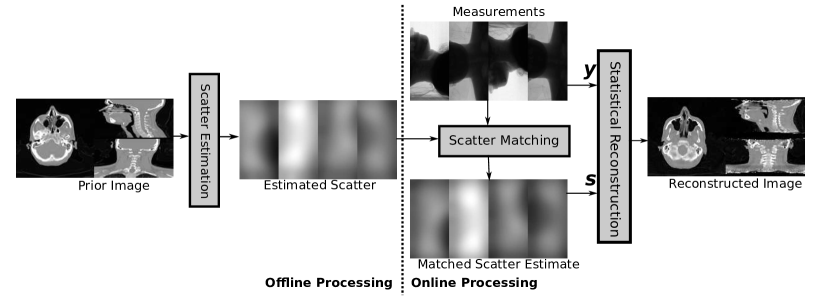

We propose that the expectation of scatter may be calculated off-line to a high accuracy based upon a prior image, then matched to the measurements during replanning. Conceptually, this is very similar to the notion of SKS/ASKS [6], where the scatter point spread function of a scanner are measured through blocks of material, and combined with convolution. Instead here, the entire global scatter profile is estimated, and simply shifted to fit the current pose of the patient. Our framework for this off-line scheme is illustrated in Figure 1.

For the match, we seek a transformation in the coordinates of detecting elements at each projection angle, for which we adopt the notation

| (7) |

where is the number of projections, is the 2D linear interpolation of the image corresponding to the projection angle of scatter estimate, is the matched estimate, and are the transformed 2D coordinates according to

| (8) |

where and are the original vector of coordinates for the detector, and are parameters we wish to calculate through the matching process.

With reference to Figure 2, each scatter projection image with coordinates is updated based on a rigid translation of an object at the centre of rotation by onto a FDK reconstruction of the measurements. We define a new set of coordinates , due to rotation of the source around by the angle by

We note that due to the projection, a translation along leads to a change in scaling, and translations in lead to shifting. If we define the distances as the lengths from source to origin and the detector respectively, the transformation to adjust the projection is